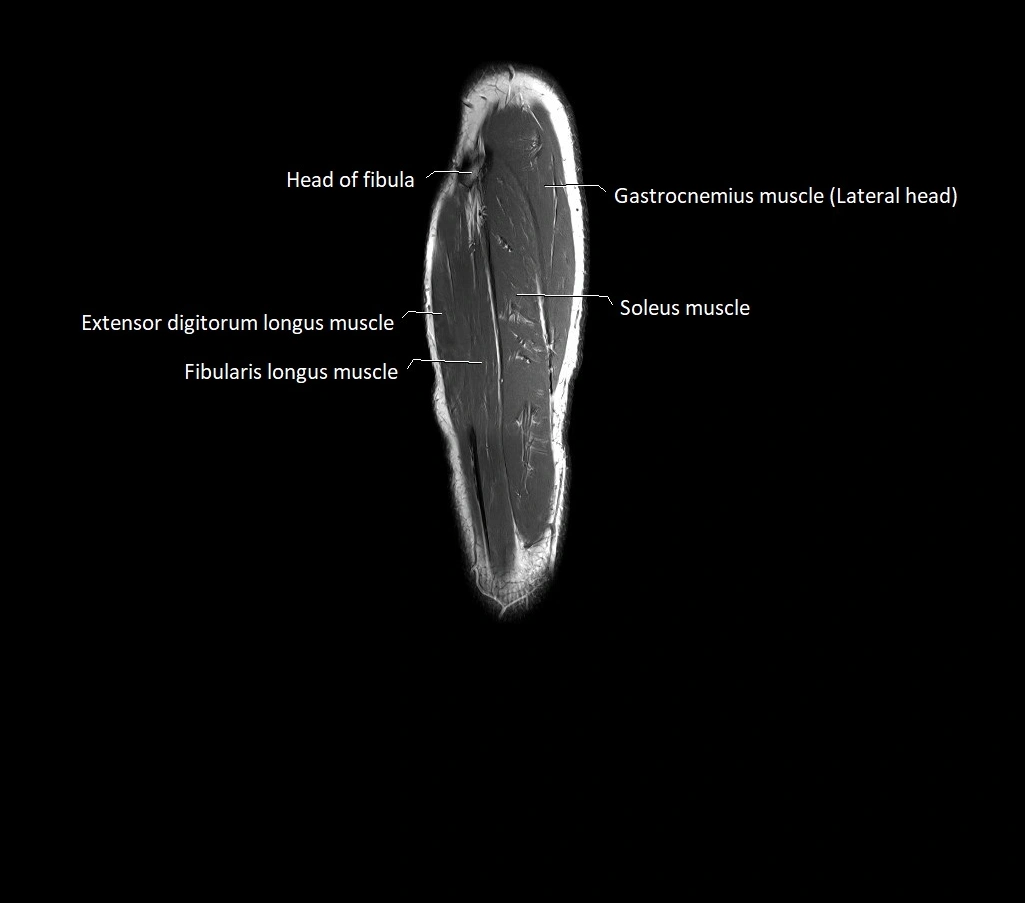

- Head of fibula

- Neck of fibula

- Extensor digitorum longus muscle

- Fibularis longus muscle (peroneus longus muscle)

- Soleus muscle

- Lateral head of gastrocnemius muscle